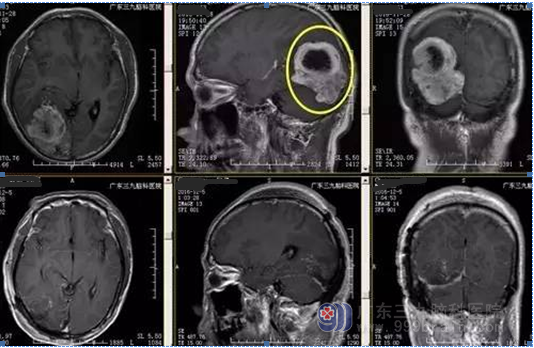

陈男子,51岁,头痛伴视物模糊2月余入院,CT提示右侧顶枕部类圆形占位,其内可见低密度影,占位效应明显,周围见低密度水肿带,MR见病变增强后明显强化,囊变区不均匀强化呈放射状分隔,病灶范围约52mm*46.8mm*64.4mm,诊断:右顶枕叶巨大脑膜瘤。

经科室研究讨论行全麻下顶枕叶巨大肿瘤切除术,手术由神经外一科主任张良主刀,术程顺利,术后病理提示血管周细胞瘤。经系统治疗后患者头痛缓解、视力较前好转。

▲手术前后MR对比

本例患者术前为头晕伴视物模糊,视物模糊与病变位于枕部损伤视觉皮质有关。MR提示呈长T1稍长T2为主异常信号, 其内示囊变区明显长T1长T2异常信号,病变中心囊变低信号,病变及其周围多发细小流空血管,增强后明显强化,囊变区不均匀强化呈放射状分隔,病灶范围约52mm*46.8mm*64.4mm。CT及MR均可见低密度及低信号囊变影,类似肿瘤中间“黑洞”。

本例肿瘤血运丰富,CTA提示与右侧大脑后动脉分支关系密切,术中出血约1500ml,术后复查见肿瘤全切除,患者目前术后神志清,肢体活动良好,视物模糊症状缓解。